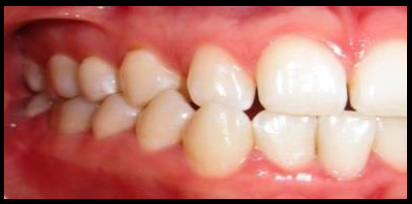

En la exploración intraoral observamos ausencia clínica del canino superior derecho y un diastema entre los dientes 12 y 14 (figura 1). Tras el estudio de la imagen panorámica (figura 2), se observa que el canino derecho superior se encuentra invertido y ubicado en la apófisis ascendente maxilar. Debido a la ubicación ectópica del diente, se solicita una tomografía axial computarizada de la estructura maxilofacial (TAC) (figura 3). Con esta ayuda diagnóstica se tendría mayor información sobre la ubicación exacta del canino derecho superior invertido (diente 13), situado en la apófisis ascendente maxilar, con respecto a las estructuras próximas o cercanas.